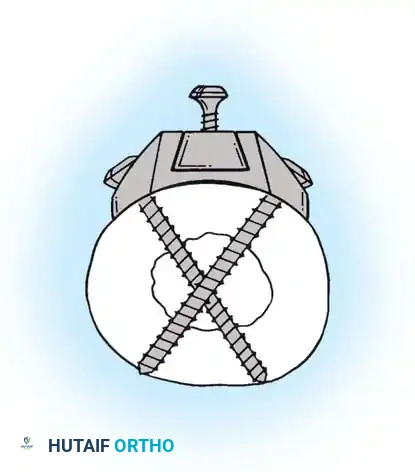

After the nail is seated, the proximal lag screw(s) are inserted through the nail into the femoral head, adhering to the same TAD principles.

Proximal locking of the cephalomedullary nail. The targeting guide ensures accurate trajectory into the femoral neck.